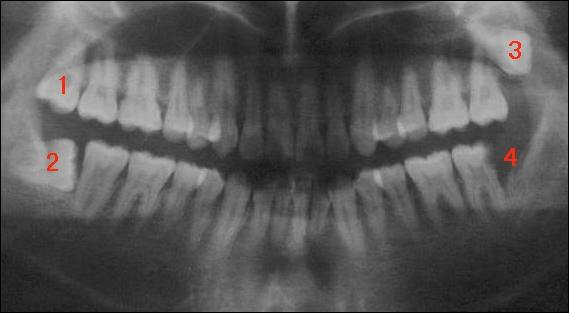

全口曲面斷層片,俗稱骷髏片

圖1位置的智齒正常生長;而下面圖2位置的牙則頂著著面的牙生長,稱為水平阻生;圖3位置的牙飛出來了,稱為垂直阻生;圖4的牙可能拔了,處于空缺狀態(tài)。因此,存在的三顆智齒都必須要拔。如果圖2的牙長的很好,那么1、2可不用拔,但只要上、下有一顆牙沒長好,那這兩顆牙全要拔。